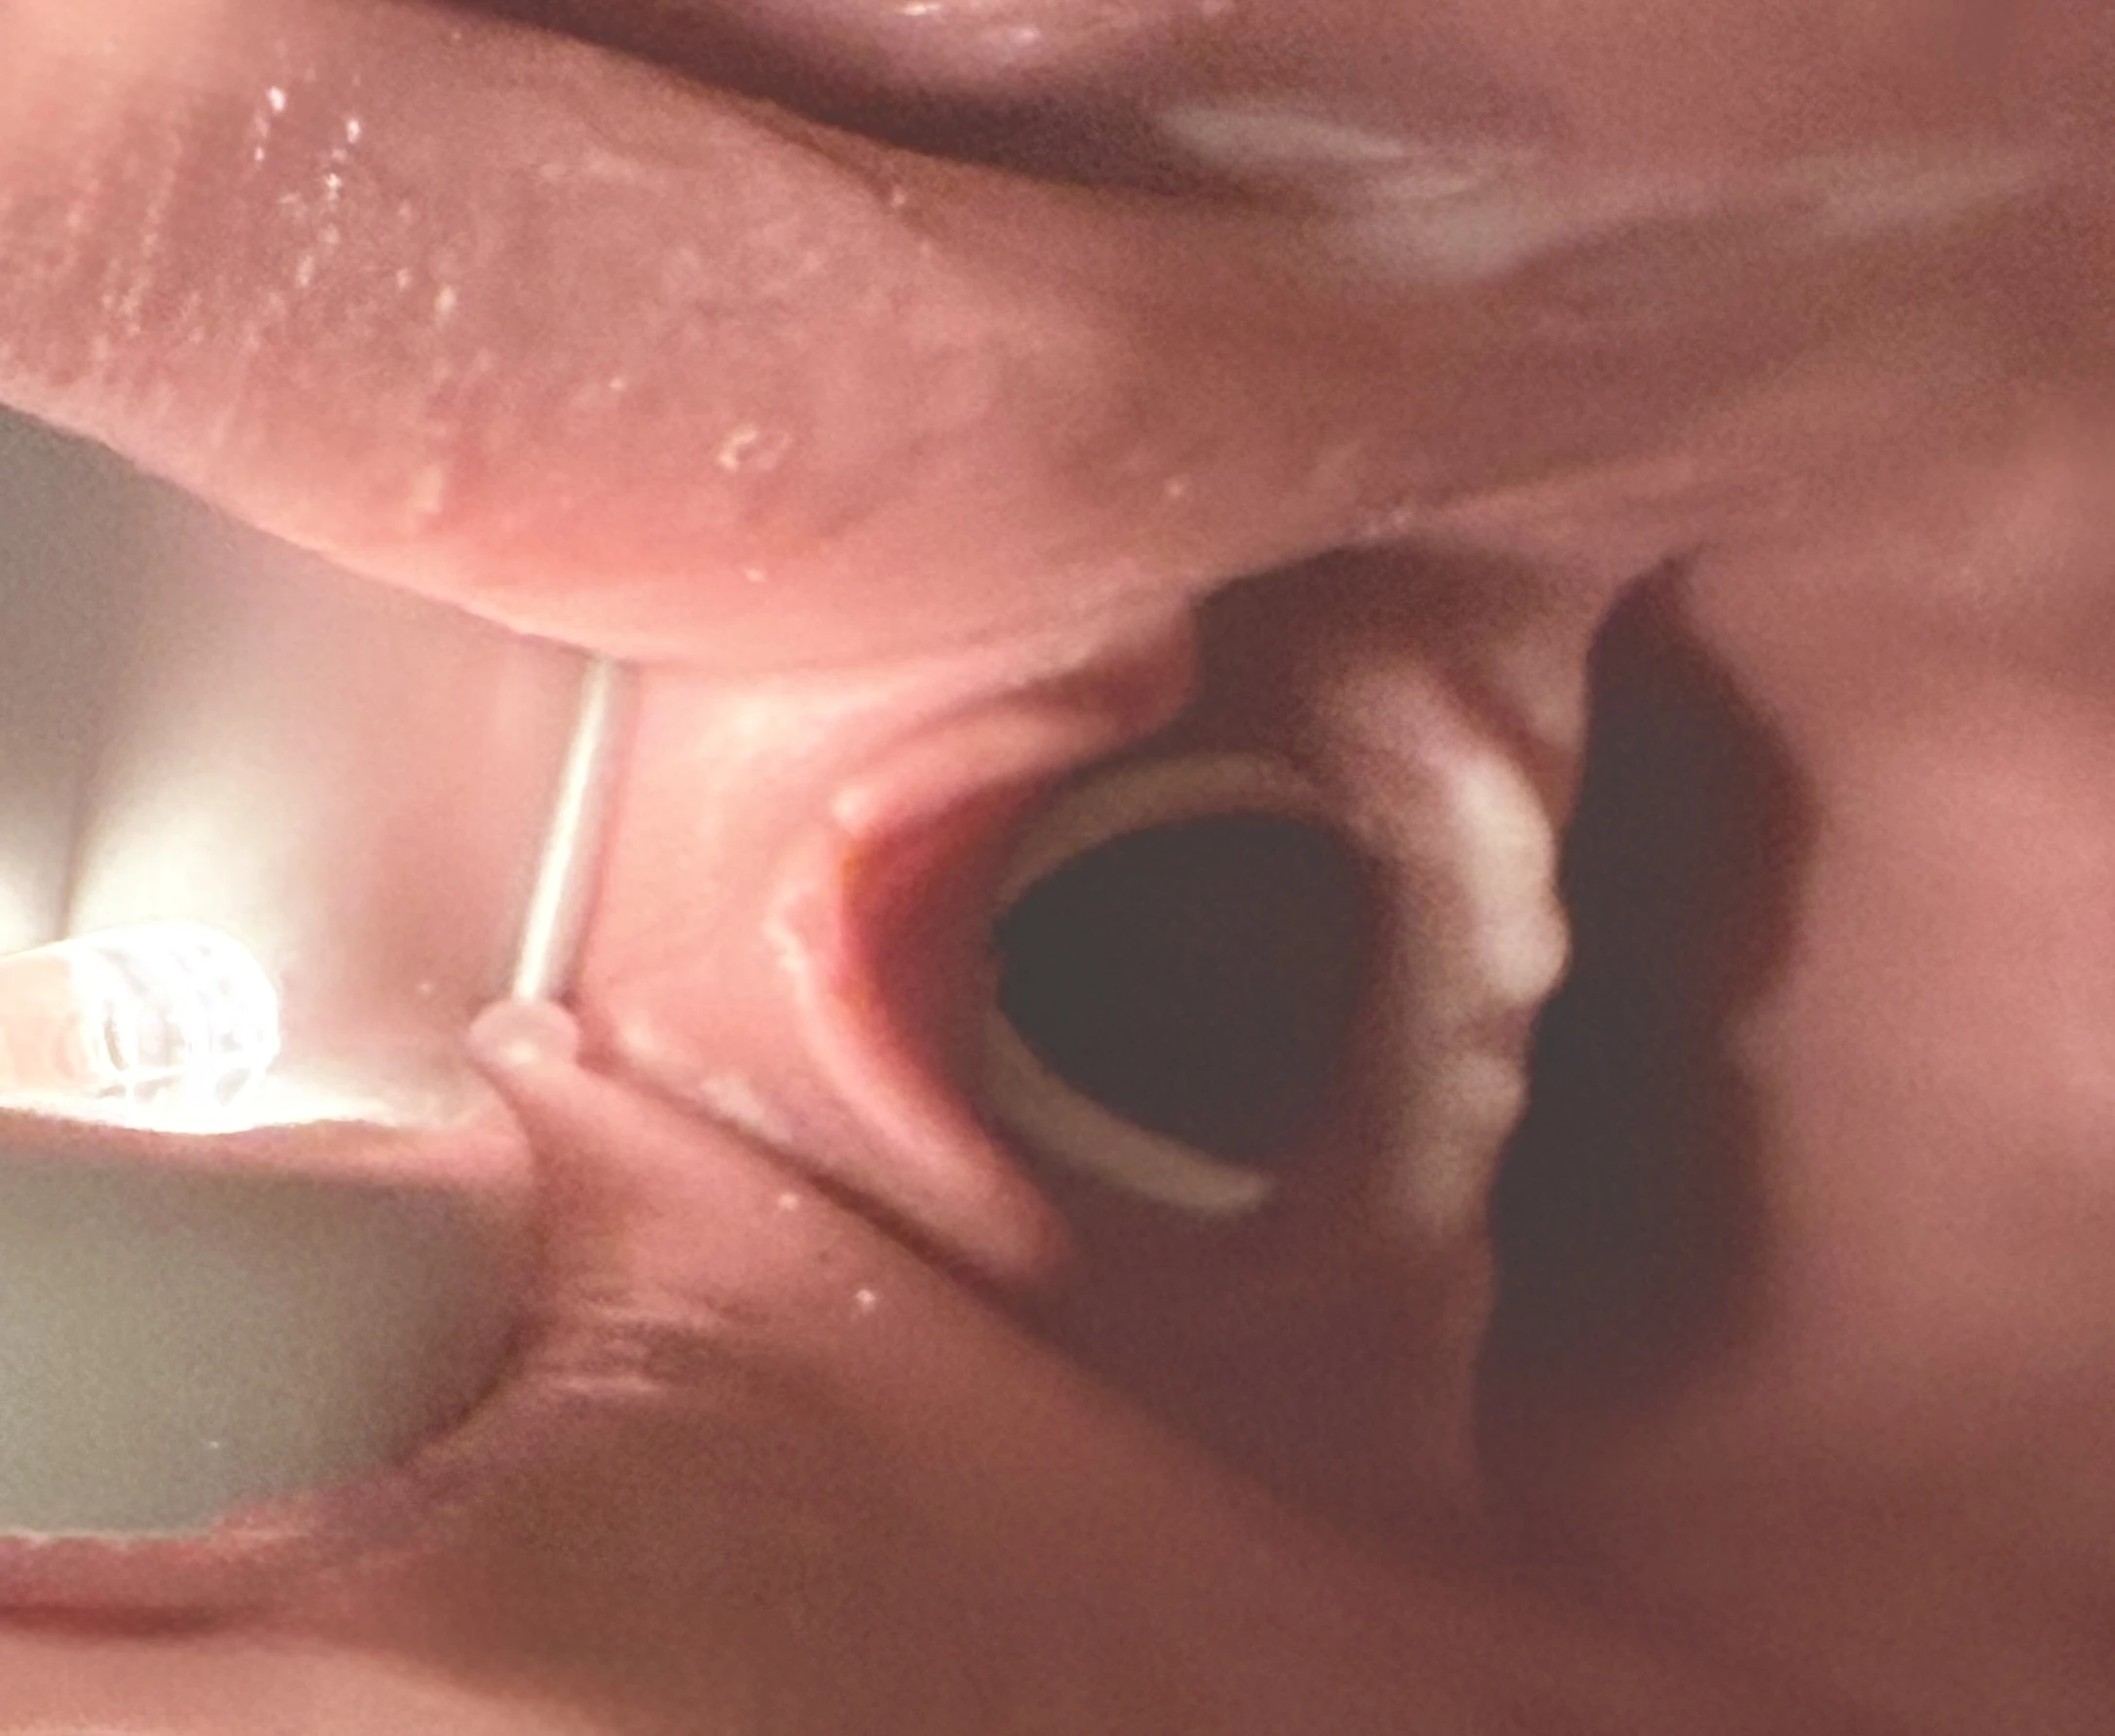

Realistisk träning med integrerad luftväg

Denna räddningsdocka med luftväg möjliggör träning av:

- Kontroll av fri luftväg

- Huvud- och haklyft

- Anpassad för luftvägshantering med nästub (näskantarell), svalgtub, i-gel/larynxmask och intubering.